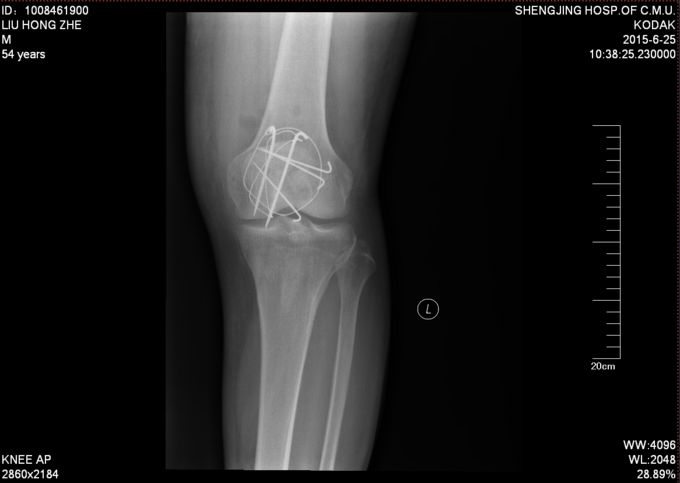

诊断:左髌骨骨折 患者入院后左膝部抬高,冷疗,消肿等对症治疗后,约一周后行左髌骨骨折切开复位张力带内固定术。